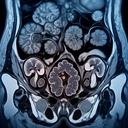

МРТ органів малого тазу

Магнітно-резонансна томографія (МРТ) органів малого тазу застосовується для детального обстеження цієї ділянки. Її призначають, щоб оцінити стан структур, як-от сечовий міхур, пряма кишка, статеві органи (матка, яєчники у жінок; простата у чоловіків), а також прилеглі тканини та судини. ### Показання для проведення МРТ малого тазу: - Підозра на новоутворення або рак...